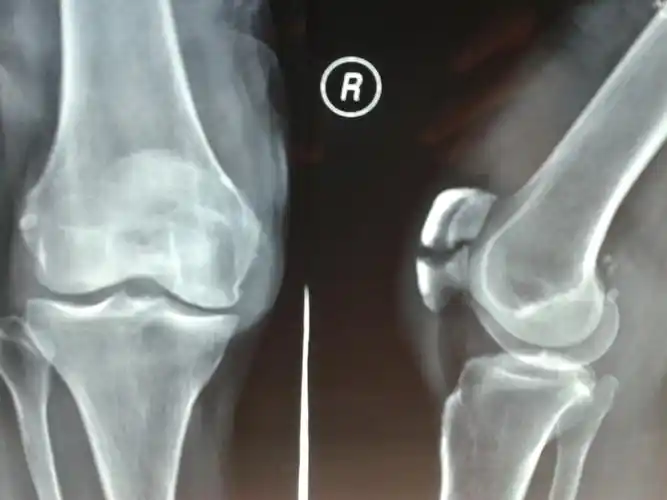

髌骨骨折术后两个月可以下地做饭吗?

这个髌骨骨折能否手术?

髌骨骨折.这样有错吗.

髌骨骨折(左)

此种髌骨骨折能手法复位吗?能保守治疗吗?